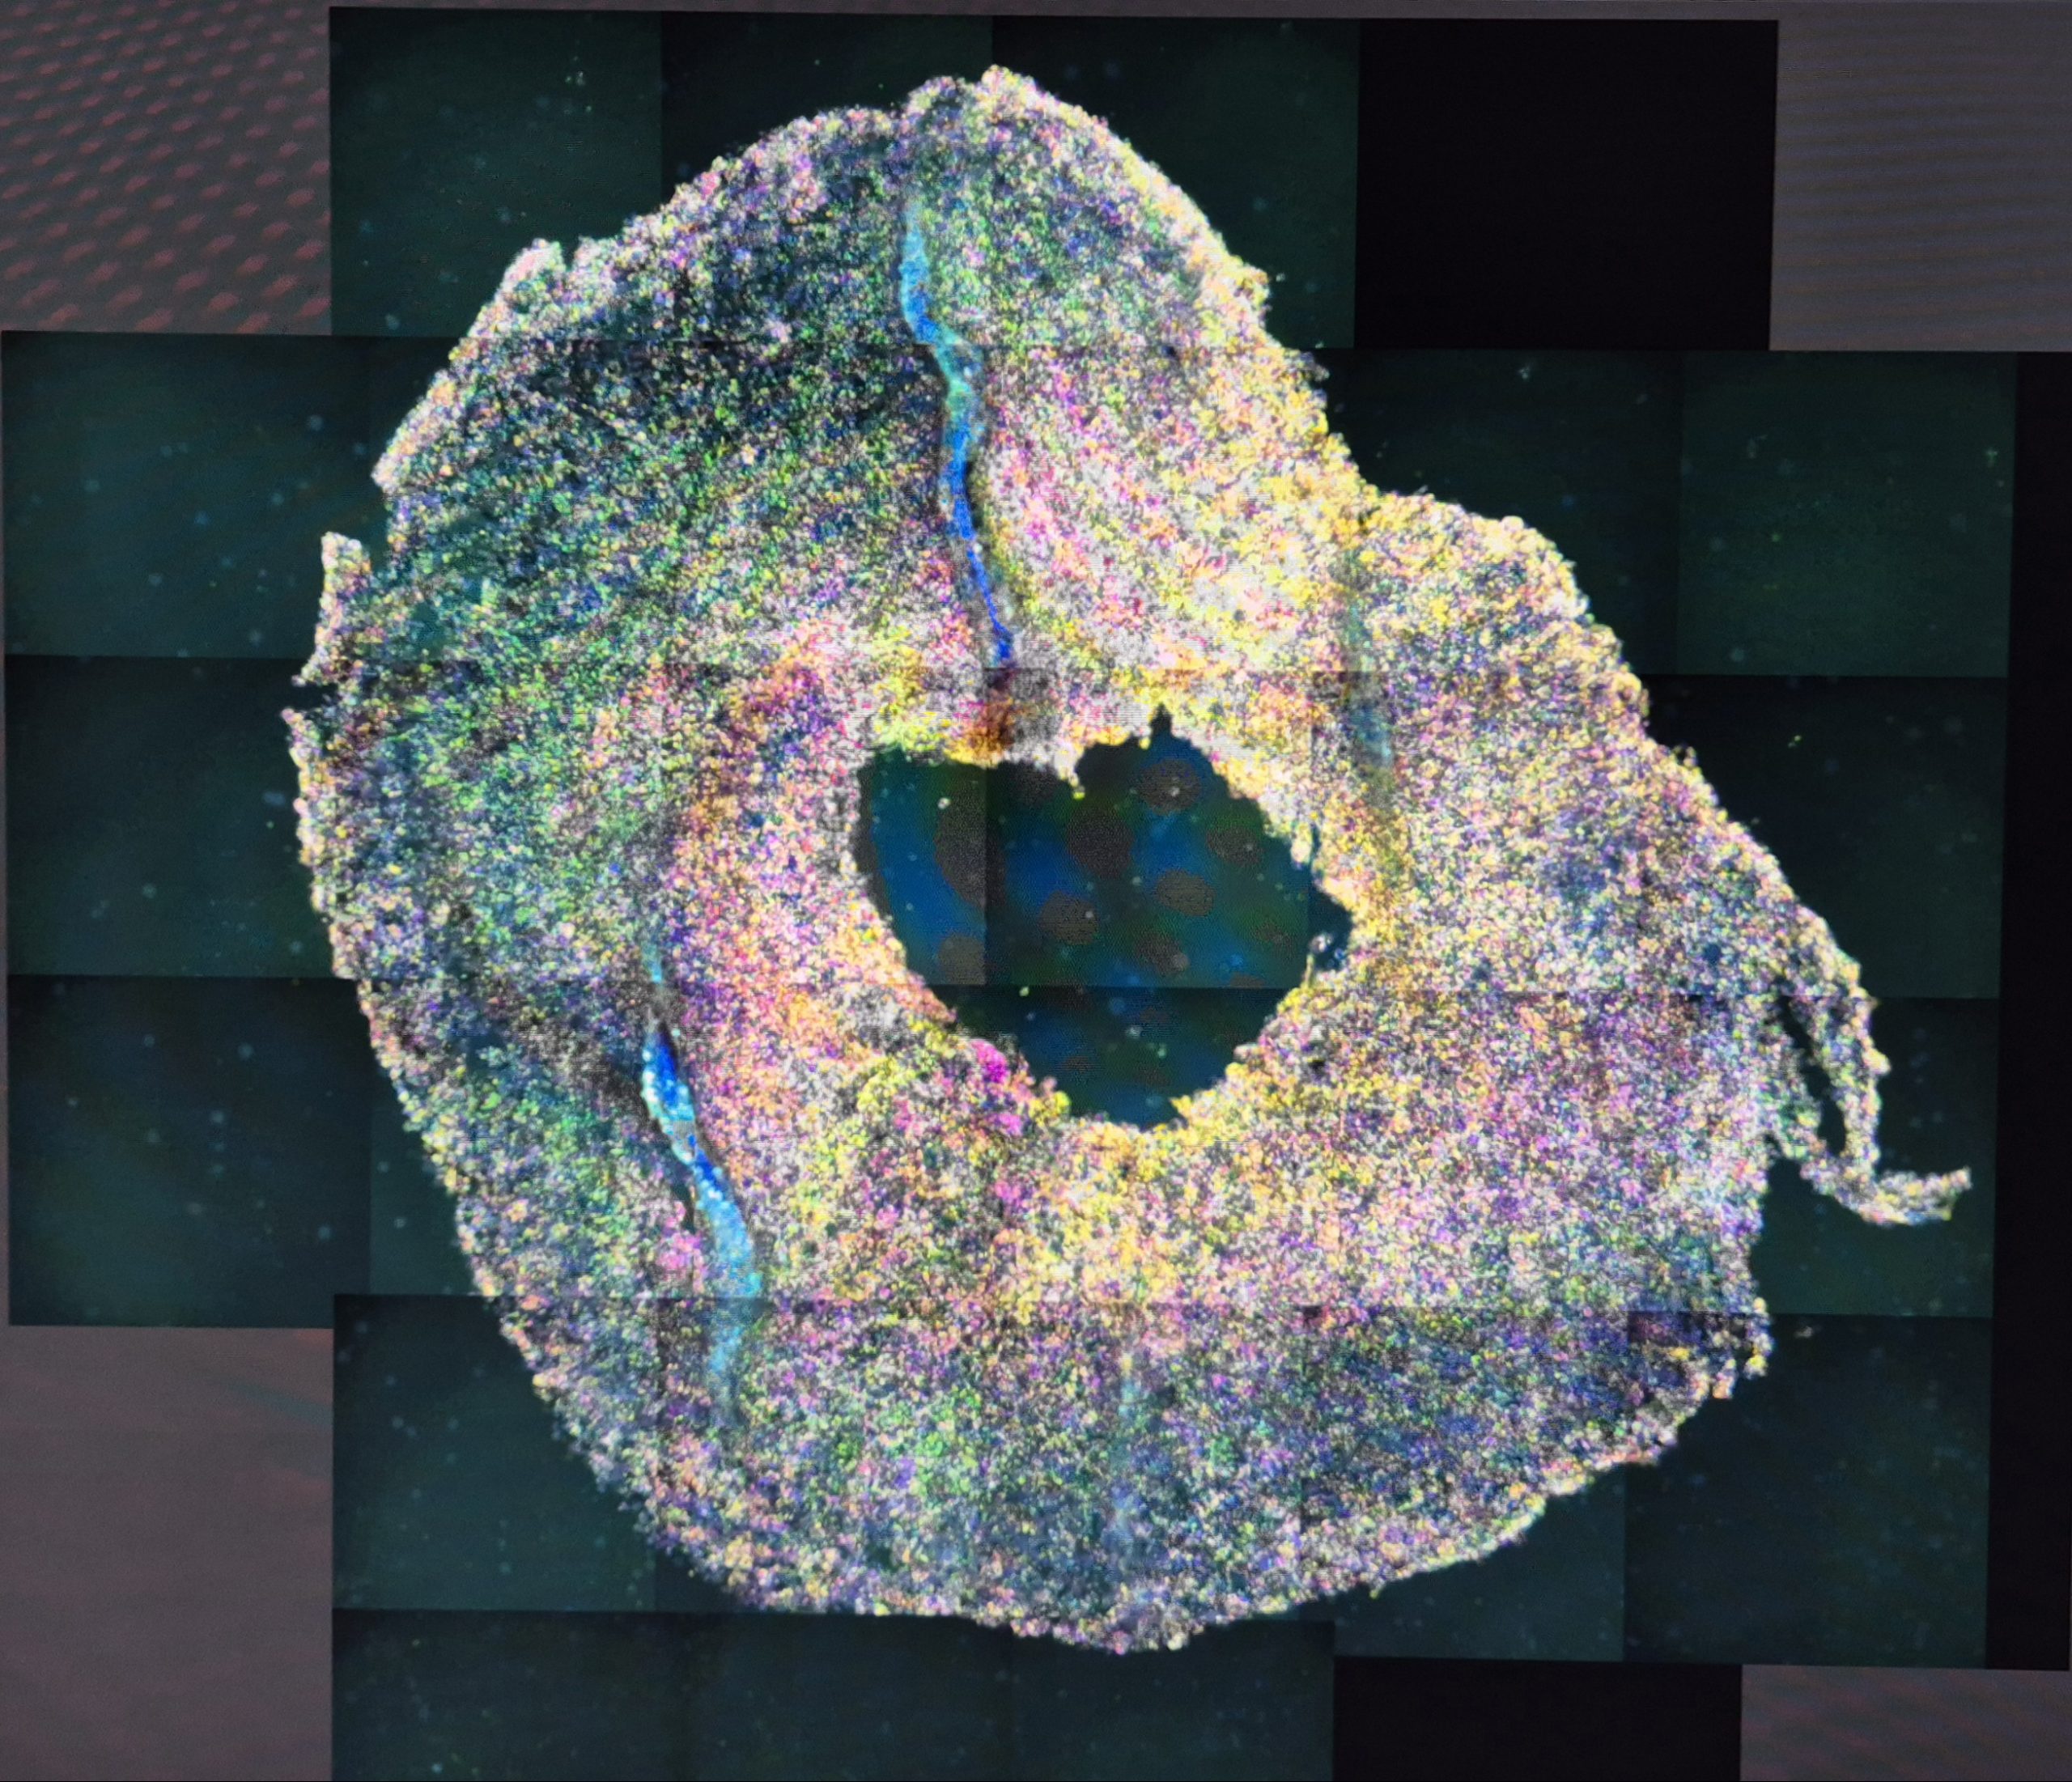

Vsa zdravila, ki jih danes uporabljamo, so bila najprej preizkušena na živalih. Toda testiranje na živalih včasih ne da pravih rezultatov in je etično sporno. Obe slabosti bi lahko rešili organi na čipu. Gre za več celic posameznih človeških organov, s katerimi simulirajo naše organe. Lani je ameriška uprava za hrano in zdravila odobrila prvo klinično preizkušanje zdravila za dve redki avtoimunski bolezni z uporabo podatkov o učinkovitosti, zbranih le iz organov na čipu. V Italiji razvijajo sklep na čipu, na katerega bodo prenesli posamezne sklepne celice bolnikov z revmatoidnim artritisom. Tako bodo lahko preizkusili, katero zdravilo je najboljše za vsakega posameznega bolnika. Kakšni so ti organi na čipu, katere organe sploh lahko imamo na njih in kakšne so njihove prednosti pred testiranjem na živalih?